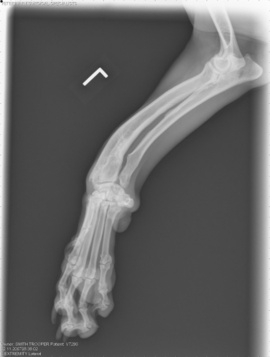

Next came X-rays, and because the clinic has a digital X-ray system, we were looking at the radiographs in less than 5 minutes. They told the full story about Trooper’s condition. This is the view of his front left leg:

In simplest terms, two bones in his leg — the radius and ulna — never grew at a normal rate. The ulna, in fact, stopped growing … and this "blocked" the radius from growing normally. The radius continued to try to grow, but had nowhere to go and ended up curving out in a ‘bowstring’ effect. Trooper’s right foot does this, too, but to a much smaller extent.